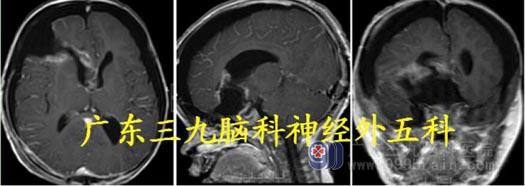

头颅MR:松果体区-三脑室-双侧侧脑室内示不规则巨大占位性病变,间杂斑片状高信号,增强后呈明显不均匀异常强化影,大小约为6.6cm×4.4cm×5.2cm,考虑畸胎瘤可能;梗阻性脑积水。

头颅CTA:松果体区巨大占位性病变并突向三脑室,并破溃入侧脑室(脂肪成分),内存在多发小血管,考虑为畸胎瘤。